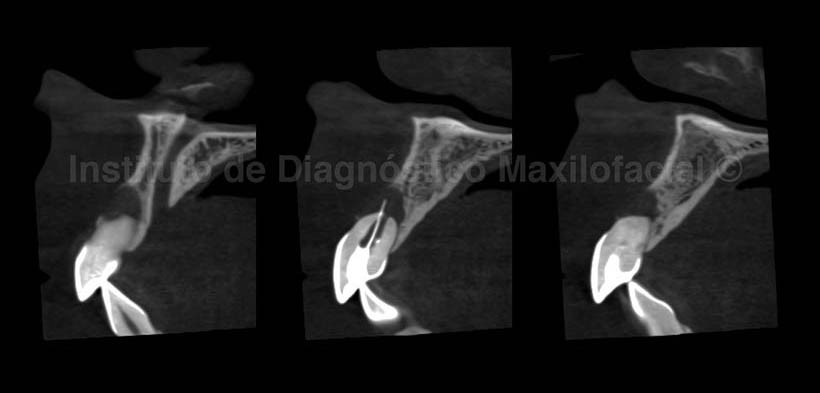

A la evaluación con Tomografía volumétrica, en los cortes sagitales (Fig.2) se observa en el interior del conducto radicular de la Pieza 2.1 y una imagen hiperdensa alargada sugerente de un cono de obturación para endodoncia, el cual ha sobrepasado el ápice condicionando la formación de un proceso osteolítico de limites parcialmente definidos, condicionando la reabsorción radicular externa y la erosión de la tabla ósea vestibular, además se observa el aumento de la densidad ósea circundante a la lesión y la cercanía de la lesión con el conducto nasopalatino.